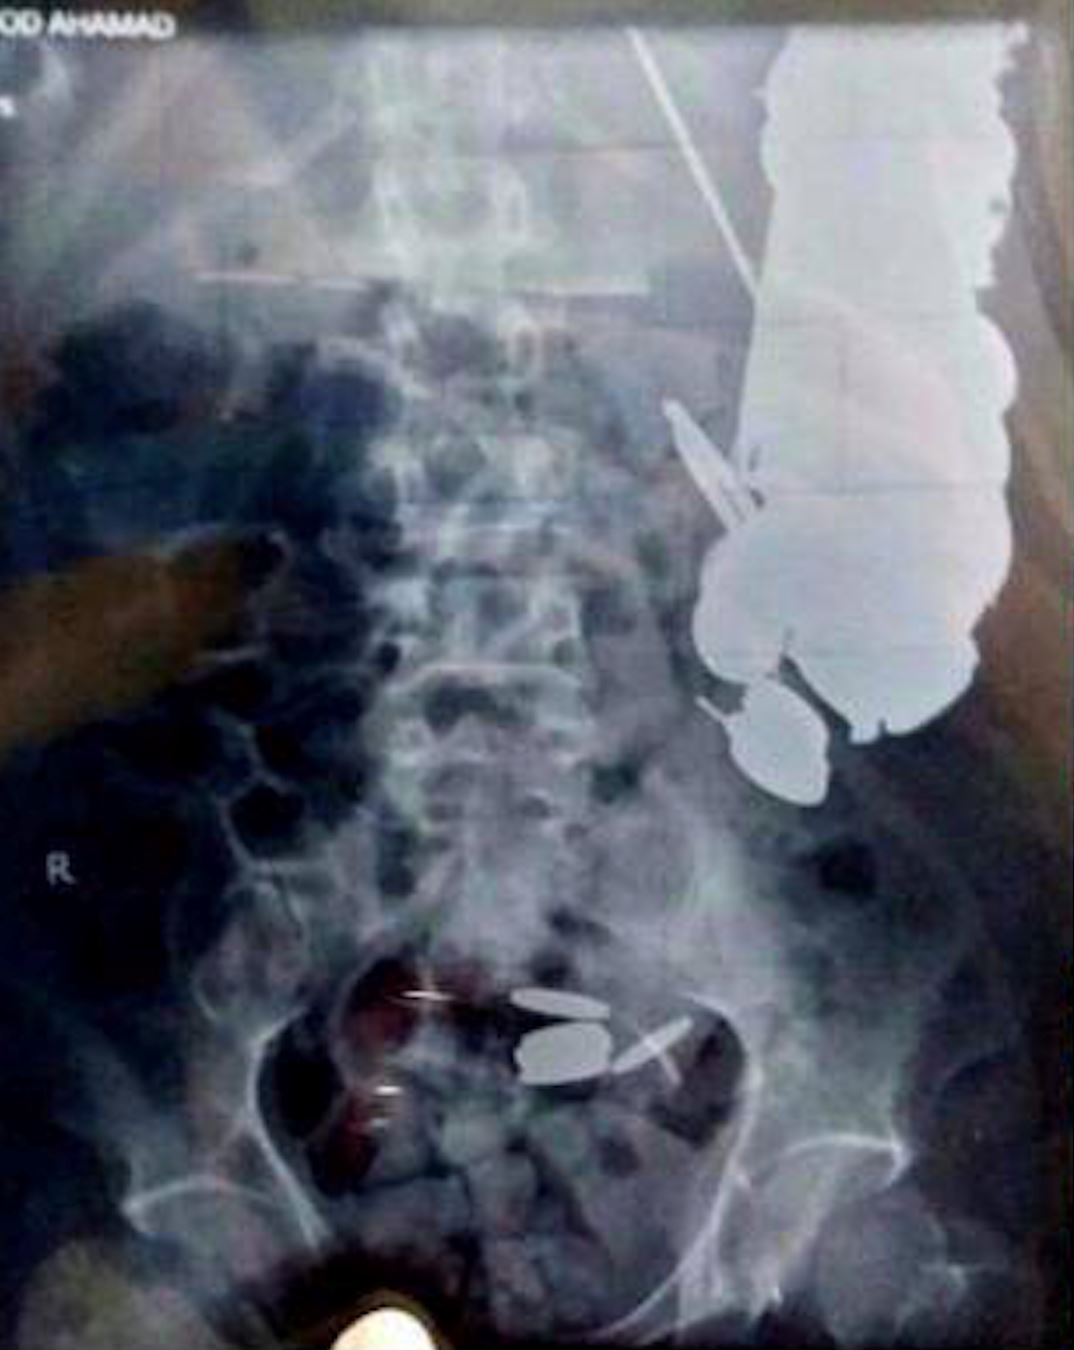

Selepas dimasukkan ke wad kecemasan, doktor terkejut apabila menemui objek asing dalam perutnya, iaitu hampir 263 keping duit syiling, 100 batang paku, pisau, kaca dan batu-batu.

Maksud Khan tidak mempunyai masalah kesihatan mental, sebaliknya beliau mempunyai tabiat pelik iaitu gemar menelan objek-objek asing seperti duit syiling dan paku, sejak dari kecil.